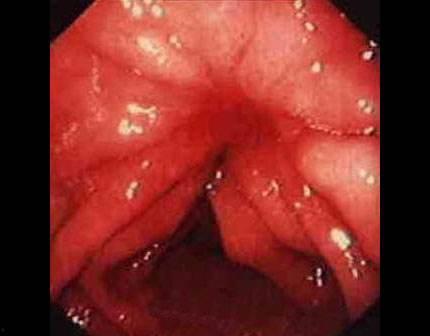

你知道吗,胃炎是一种常见的胃部疾病,主要是因为胃黏膜受到刺激或损伤引起的。吃瓜的时候,我们往往喜欢边吃边说笑,这样很容易导致吞咽过快,瓜籽、瓜皮等硬物刺激胃黏膜,引发胃炎。

据《中国慢性胃炎诊疗指南》显示,我国慢性胃炎的患病率高达30%以上,而且这个数字还在逐年上升。我那胃疼得简直要了我的命,真是后悔当初贪嘴啊!